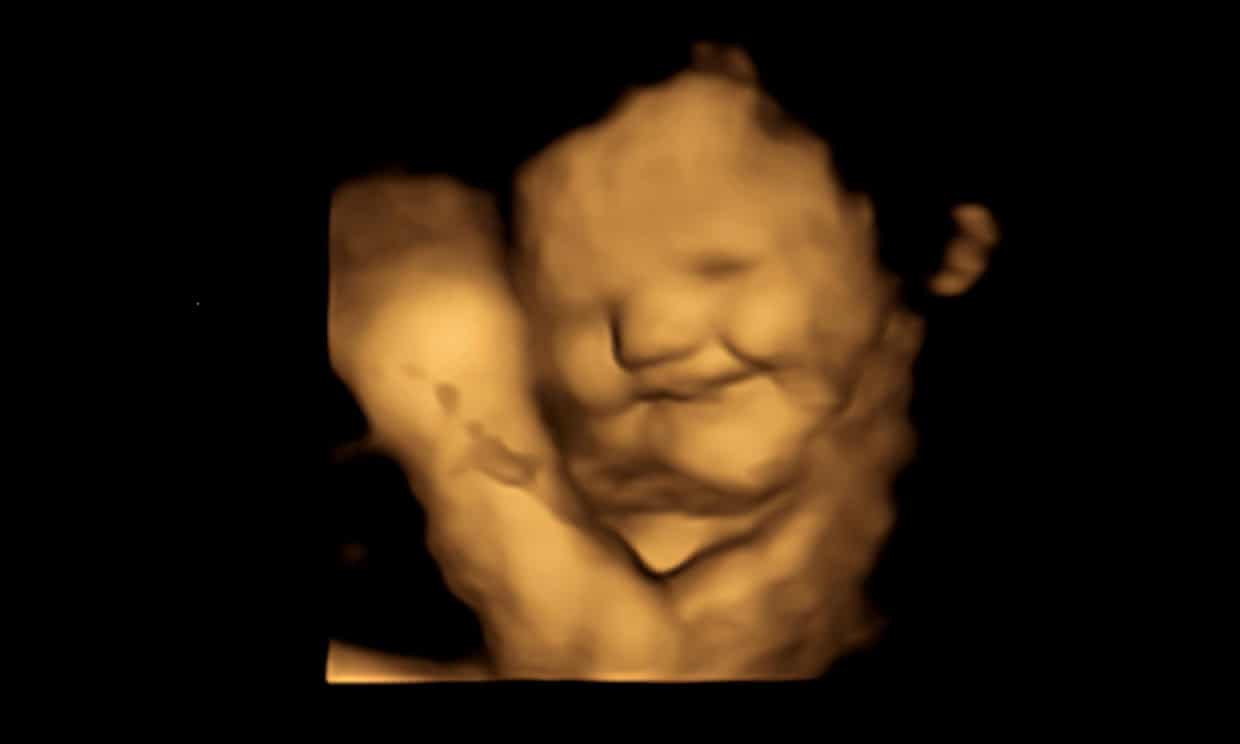

Плоды демонстрировали плачущее выражение лица примерно в два раза чаще, когда мать употребляла капсулу капусты, чем морковь. Фотография: FETAP (Fetal Taste Preferences) Study/Fetal and Neonatal Research Lab/Durham University/PA

Среди результатов команда обнаружила, что плод плачет примерно в два раза чаще, когда мать употребляет капсулу капусты, по сравнению с капсулой моркови или без капсулы. Однако, когда мать съедала морковную капсулу, плод принимал смехоподобное выражение лица примерно в два раза чаще, чем когда мать глотала капсулу капусты или не глотала капсулу.